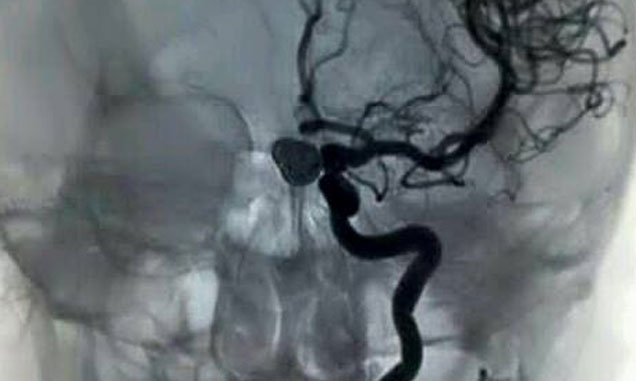

Avrasiya Hospitalda daha bir uğurlu əməliyyat İnvaziv Radioloq Tibb Elmləri üzrə Fəlsəfə Doktoru İLYAS HƏSƏNOV və Tibb Elmləri üzrə Fəlsəfə Doktoru invaziv neyro-radioloq RUSLAN PİŞANOV tərəfindən həyata keçirildi.44 yaşlı bir xəstədə beyin damarının qiqant anevrizması endovaskular üsul ilə uğurla embolizasiya edildi.